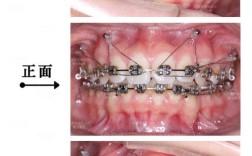

T型曲/摇椅曲矫治器:

(图片来源网络,侵删)- 原理: 在主弓丝(通常为0.016"或0.018"不锈钢方丝)上弯制一个垂直向的T型曲或一个连续的摇椅形弯曲。

- 作用: 当弓丝放入托槽槽沟时,T型曲或摇椅曲的垂直部分会对后牙产生向下的压入力,需要高支抗来抵抗前牙的伸长和后牙的支抗丧失。